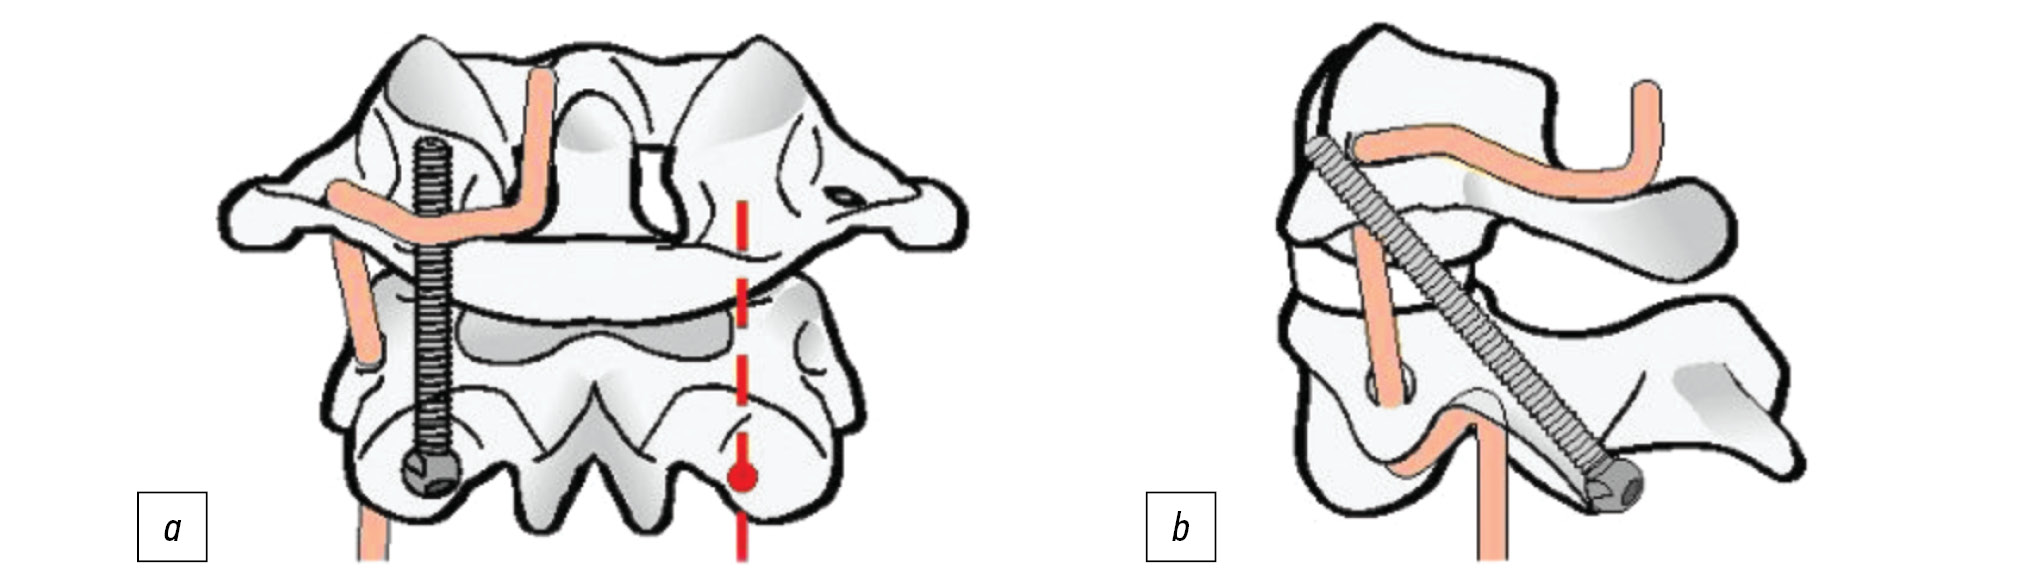

F. Magerl и P.S. Seemann в 1979 г. предложили методику задней трансартикулярной фиксации СI-СII винтами (рис. 5) [27]. Данная техника показала лучшее сращение, чем субламинарная проволочная фиксация [3].

Рис. 5. Методика фиксации СI-СII по Magerl. a — вид сзади, b — вид сбоку.

Fig. 5. C1-C2 fixation technique by Magerl. a — back view, b — side view.

C.A. Dickman и V.K. Sonntag в 1998 г. в большой серии исследований с участием 121 пациента, у 9 из которых была зубовидная кость и которым проводилась СI-СII фиксация с задним спондилодезом с применением задней трансартикулярной либо субламинарной проволочной фиксации, продемонстрировали уровень формирования костного блока, равный 98%, при использовании этой техники по сравнению с 86% при использовании задней субламинарной проволочной фиксации [28].

Хотя существенной разницы в частоте формирования костного блока при использовании трансартикулярной винтовой фиксации и проведении полиаксиальных винтов через боковые массы СI и через pars interarticularis транспедикулярно в СII нет, имеются ограничения в плане техники. Во-первых, перед проведением трансартикулярного винта необходимо привести в норму соотношения в атлантоаксиальном суставе, что означает достижение редукции. Во-вторых, правильный угол проведения винта в случаях, когда у пациента имеется выраженная кифотическая деформация грудного отдела, может быть не достигнут. И наконец, примерно пятая часть пациентов с аномалиями краниовертебрального перехода имеют другие костные аномалии в данной области либо аномальное прохождение позвоночной артерии, что увеличивает вероятность её травмирования при использовании этой техники [29, 30].